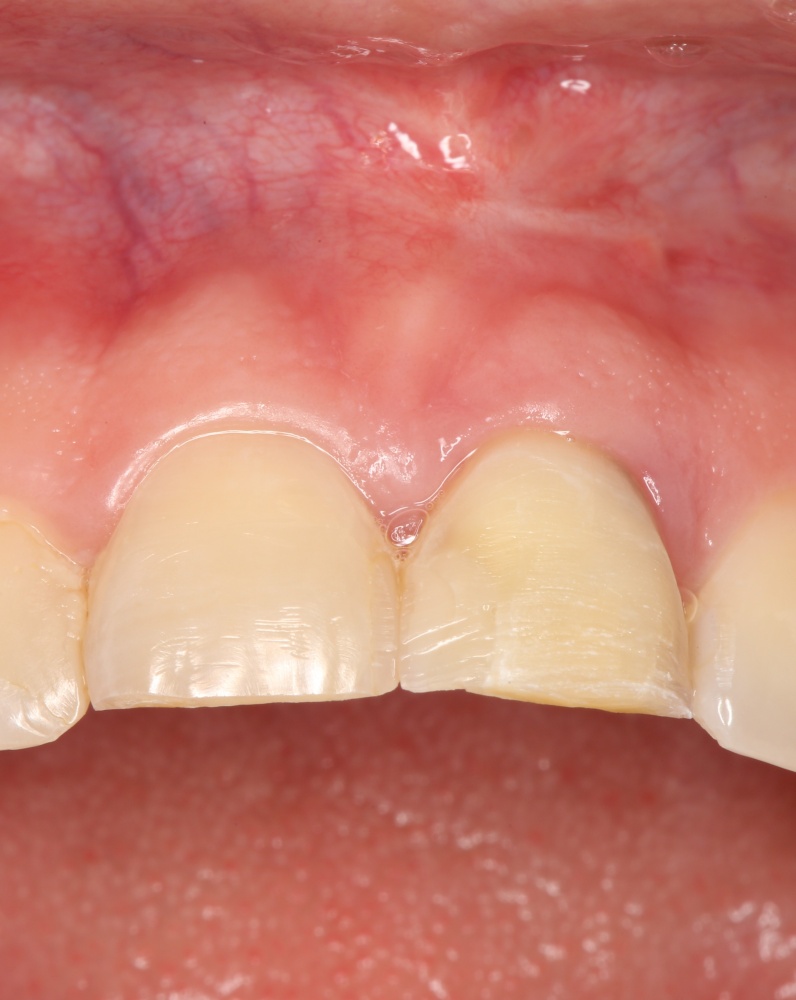

Рекомендации по установке имплантов. Для всех. Часть V.